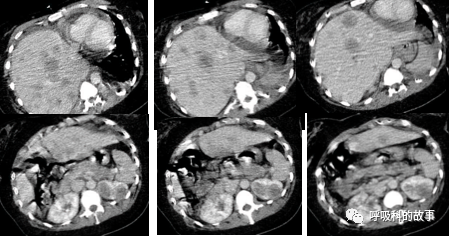

患者肝脏体积增大,里面密密麻麻分布着大小不一的结节,右侧膈肌明显抬高,使得右肺体积明显缩小;右肺门与肺动脉交界处有一个肿块(如下图):